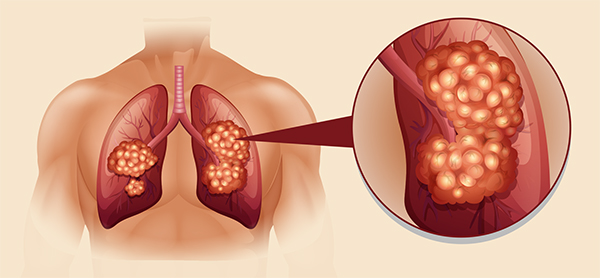

폐암은 국내 암 사망률 1위로, 과거에는 흡연이 폐암의 주요 원인이었지만 최근에는 비흡연자의 폐암 발병이 크게 증가하고 있습니다. 폐암은 오랜 기간 암 사망률 1위를 차지하고 있지만, 의학의 발전으로 생존율이 높아지고 있습니다. 그러나 초기 단계에서 올바르게 관리하는 것이 중요합니다. 폐암의 초기 징후가 무엇인지, 폐암에 좋은 음식은 무엇인지 알아두는 것이 좋습니다.